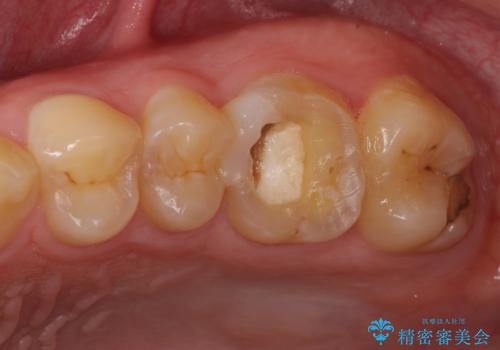

根管治療中の転院 奥歯のオールセラミック治療

- ラバーダムや顕微鏡を用いた根管治療を希望されて、転院された患者様です。

前医にて神経を取り除いた処置を行った際、ラバーダムが使用されなかったとのことで転院されてきました。

根管治療を実施した後、フルジルコニアクラウンに補綴することとしました。